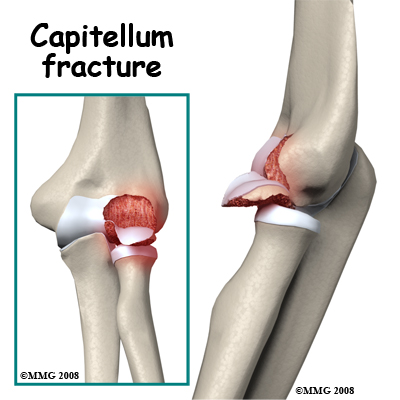

Fracture of the Capitellum: This is the rounded end of the humerus on the outer side of the elbow. It forms a joint with the radial head and is important for the stability of the joint. A piece of the capitellum can be broken off when the elbow is dislocated or when force is transmitted up the radius as a result of a fall on the outstretched hand. The floating piece may jam in the joint, limiting movement. The irregular joint surface may cause long-term wear. It is often necessary to operate on the elbow to retrieve any loose pieces following this fracture and it is sometimes possible to fix them back in position.

Capitellum Fractures. With this injury there is a high likelihood of intra-articular loose bodies that may jam in the elbow joint and damage it. The joint may be opened to retrieve the loose fragments or this may be done with an arthroscope. If the fragment is one large piece and has enough bone attached, it may be possible to fix it back in position with a screw buried into the bony part of the fragment. In this case it is often desirable to remove the screw once the fracture has healed. Healing may take some time as the bony part of the fragment has lost its blood supply (avascular) and is dead. The dead bone forms a framework on which new living bone grows to support the joint surface again but this takes time. It is not unusual to have a poor long-term result from a capitellum fracture with arthritis of this part of the elbow joint. Intra-Articular Distal Humerus Fractures: These are the most challenging fractures of the region to treat. Each fracture is different; however the rationale for most fractures is to restore the joint surface exactly then fix the joint to the shaft of the humerus securely. If the reduction is aligned as anatomically correct as possible it forms a stronger and better fix, but this alignment is not as important as the restoration of the joint surface itself where some inaccuracy is permissible. There are usually pins or screws extending from one condyle to the other, which join the joint fragments, and plates along the columns to fix the joint to the shaft of the humerus.